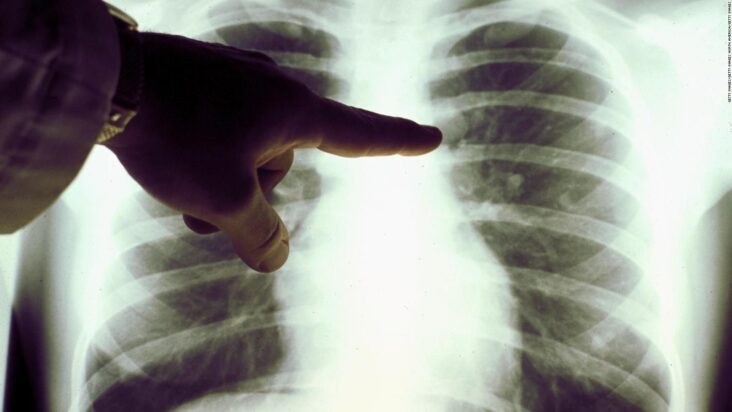

The patients recovered from the COVID-19 reduce lung capacity by up to 30 percent and have problems such as shortness of breath to the brisk and fast pace, according to a study implemented by the Hospital Authority of Hong Kong (China).

“They gasp if they speed up,” Tsang explained, adding that after recovery, “some patients may have a reduction in their lung capacity of between 20% and 30%.”